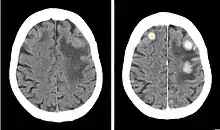

Ioxaglic acid (trade name Hexabrix) is pharmaceutical drug used as an iodinated contrast medium for X-ray imaging. It has low osmolality (relatively few molecules per volume), typically resulting in fewer side effects than high-osmolality media.[1] It is manufactured by Guerbet, but marketing in the US has been discontinued.[2] As of 2021, it may still be available in some European countries.[3]

Uses include angiography (imaging of blood vessels, including those of the brain and heart), arthrography (imaging of joints), urography (imaging of the urinary system), hysterosalpingography (imaging of the uterus and fallopian tubes), imaging of the gastrointestinal tract, and endoscopic retrograde cholangiopancreatography (ERCP; imaging of the biliary and pancreatic ducts).[4]

Ioxaglic acid is an iodine-containing, water-soluble radiocontrast agent. The iodine atoms readily absorb X-rays, resulting in a higher contrast of X-ray images. It has a low osmolality of 600 mosm/kg water at 37 °C (99 °F), meaning that the solution has a relatively low concentration of molecules; this is usually associated with fewer adverse effects than high-osmolality contrast agents.[2][4]